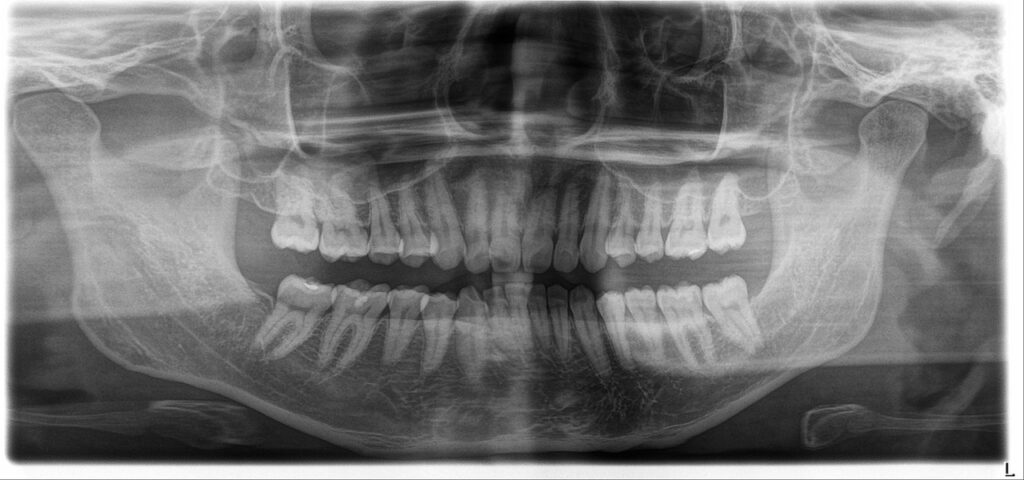

骨造成(GBR)とは

GBRとは、Guided Bone Regeneration(骨誘導再生療法)の略称で、失われたあごの骨を再生させる歯科治療です。

インプラント治療を行う際、歯を支えるために骨の厚みが不足している方を対象に、人工的に骨を造成するためにこの技術を使用します。GBRは、インプラントをしっかりと固定させ、治療を可能にするために不可欠な専門的な骨造成術の一つです。

骨造成(GBR)の治療の流れ

GBRは、まずCTスキャンなどによる画像診断で骨の量と質を評価し、必要な骨造成の量を計画します。手術は局所麻酔下で行い、歯茎を切開して骨欠損部に人工骨などの骨再生材料を配置します。さらに特殊な膜で覆い、歯茎を縫合閉鎖して、新しい骨の成長を促します。ほとんどの場合、このGBRはインプラントの埋入と同時に実施され、骨がしっかりと完成・結合すれば、人工歯を装着する次の段階へと移行します。